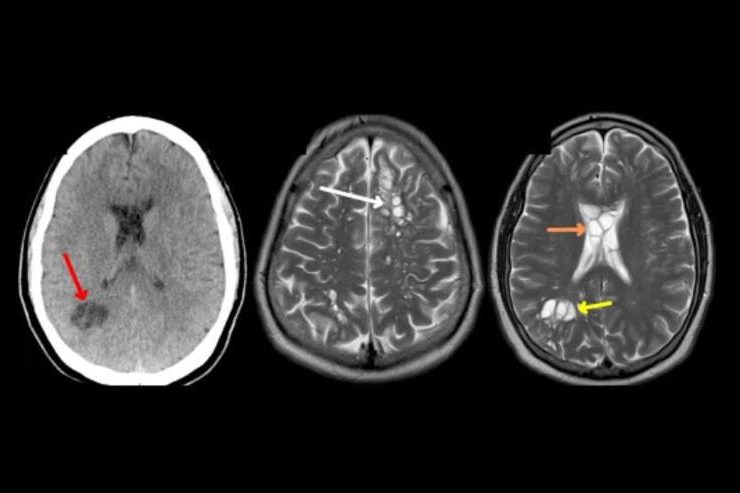

Poco después estás personas empezaron a presentar fiebre, dolores musculares intensos, hinchazón alrededor de los ojos y recuento alto de glóbulos blancos. Los síntomas empeoraban cada vez más por lo que fueron al hospital, ahí se le diagnosticó a los 6 con triquinelosis, que en palabras simples es infección cerebral por gusanos.